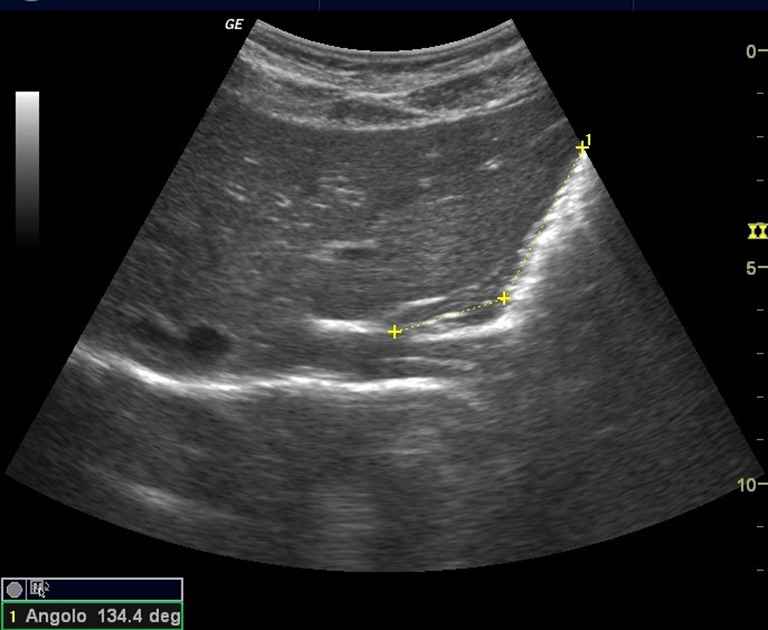

- Ângulo gastroesofágico de His;

Entre os principais achados descritos estão medidas do esôfago abdominal, do ângulo de His, da parede esofágica e da dinâmica do esvaziamento e da acomodação gástrica, embora os valores de referência ainda não sejam bem padronizados.

Entre os parâmetros ultrassonográficos descritos, destacam-se:

- Avaliação do ângulo gastroesofágico de His.

Alterações nessas medidas têm sido associadas ao refluxo gastroesofágico em diferentes estudos, sugerindo relevância anatômica e funcional.